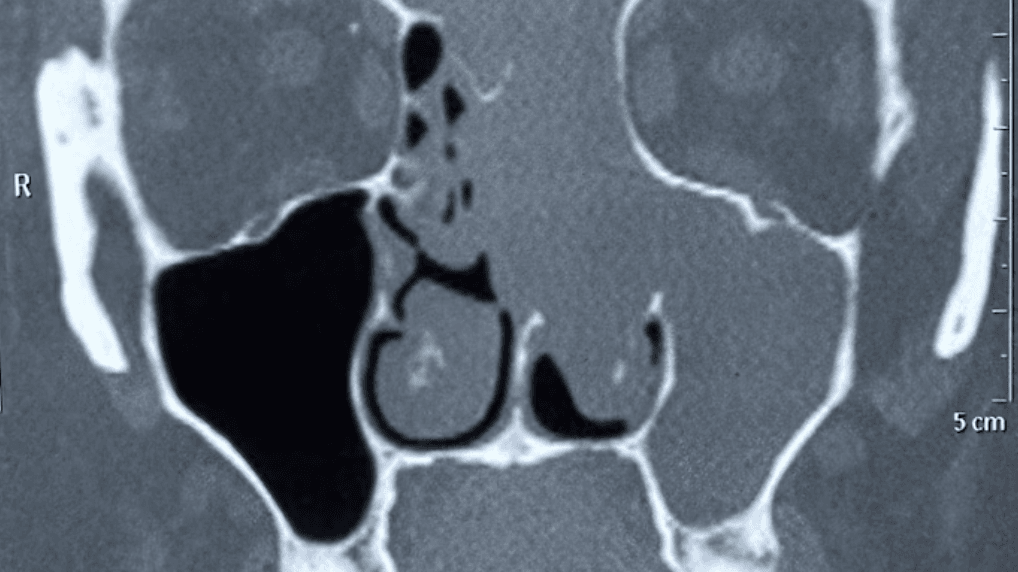

Introduction Medicine never ceases to amaze—and sometimes, reality sounds stranger than fiction.In one such extraordinary case, a 33-year-old woman from Delhi faced an unimaginable condition: a portion of her brain tissue had slipped into her nasal cavity, causing months of severe nasal blockage and fluid discharge. At HCMCT Manipal Hospital, Delhi, a team of expert […]